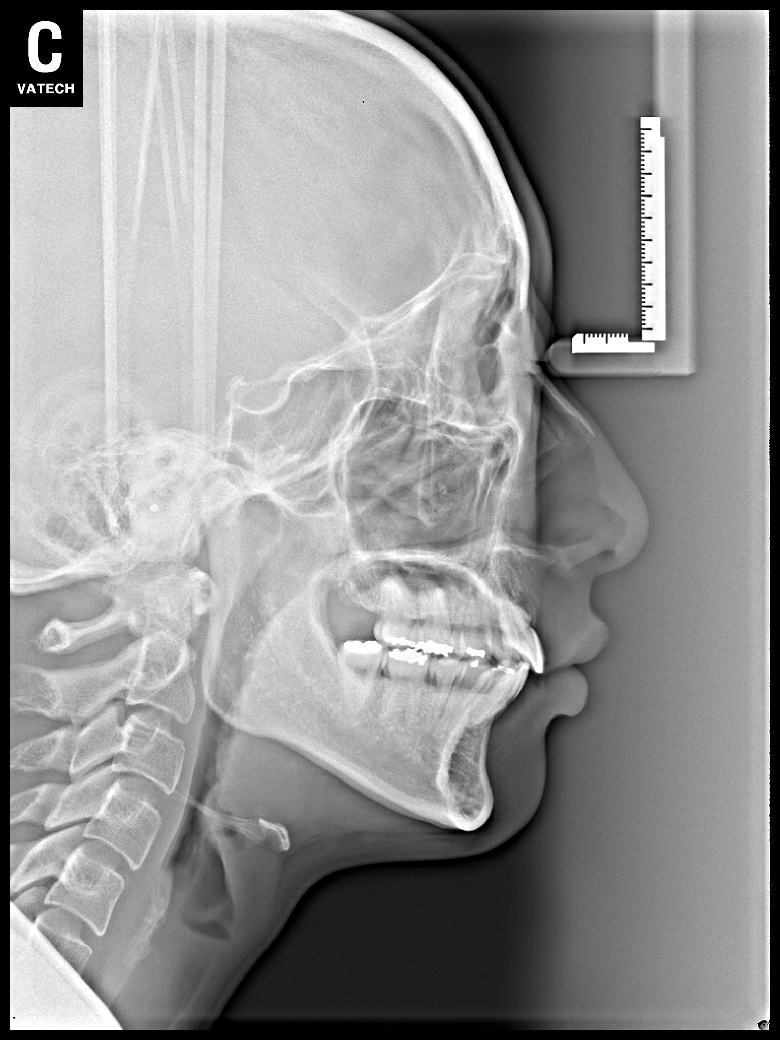

치료 전 사진입니다.